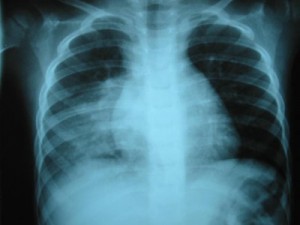

Los efectos de los sedantes en el organismo han estado varias veces bajo el microscopio y se han relacionado con la aparición de numerosas enfermedades como consecuencia de la depresión a la que se somete el sistema nervioso. Al respecto, un reciente estudio publicado en la revista Thorax afirma que los sedantes también aumentan el riesgo de padecer neumonía.

Para llegar a estos resultados los investigadores analizaron a casi 5.000 pacientes con neumonía y a 29.500 personas sin esta enfermedad. Luego de comparar varios estilos y hábitos de vida y salud comprobaron que en el grupo de pacientes con neumonía se evidenció un elevado consumo de sedantes como las benzodiazepinas.

De esta manera, se asoció el consumo de benzodiazepinas con un 54% de riesgo mayor de desarrollar neumonía en algún momento de la vida. Así mismo, se destacó que el riesgo de morir al mes del diagnóstico de una neumonía en los pacientes que consumían benzodiazepinas era de un 22% mayor y el riesgo de morir en un período de tres años luego del diagnóstico de un 32% en comparación con aquellos que no consumen estos sedantes.